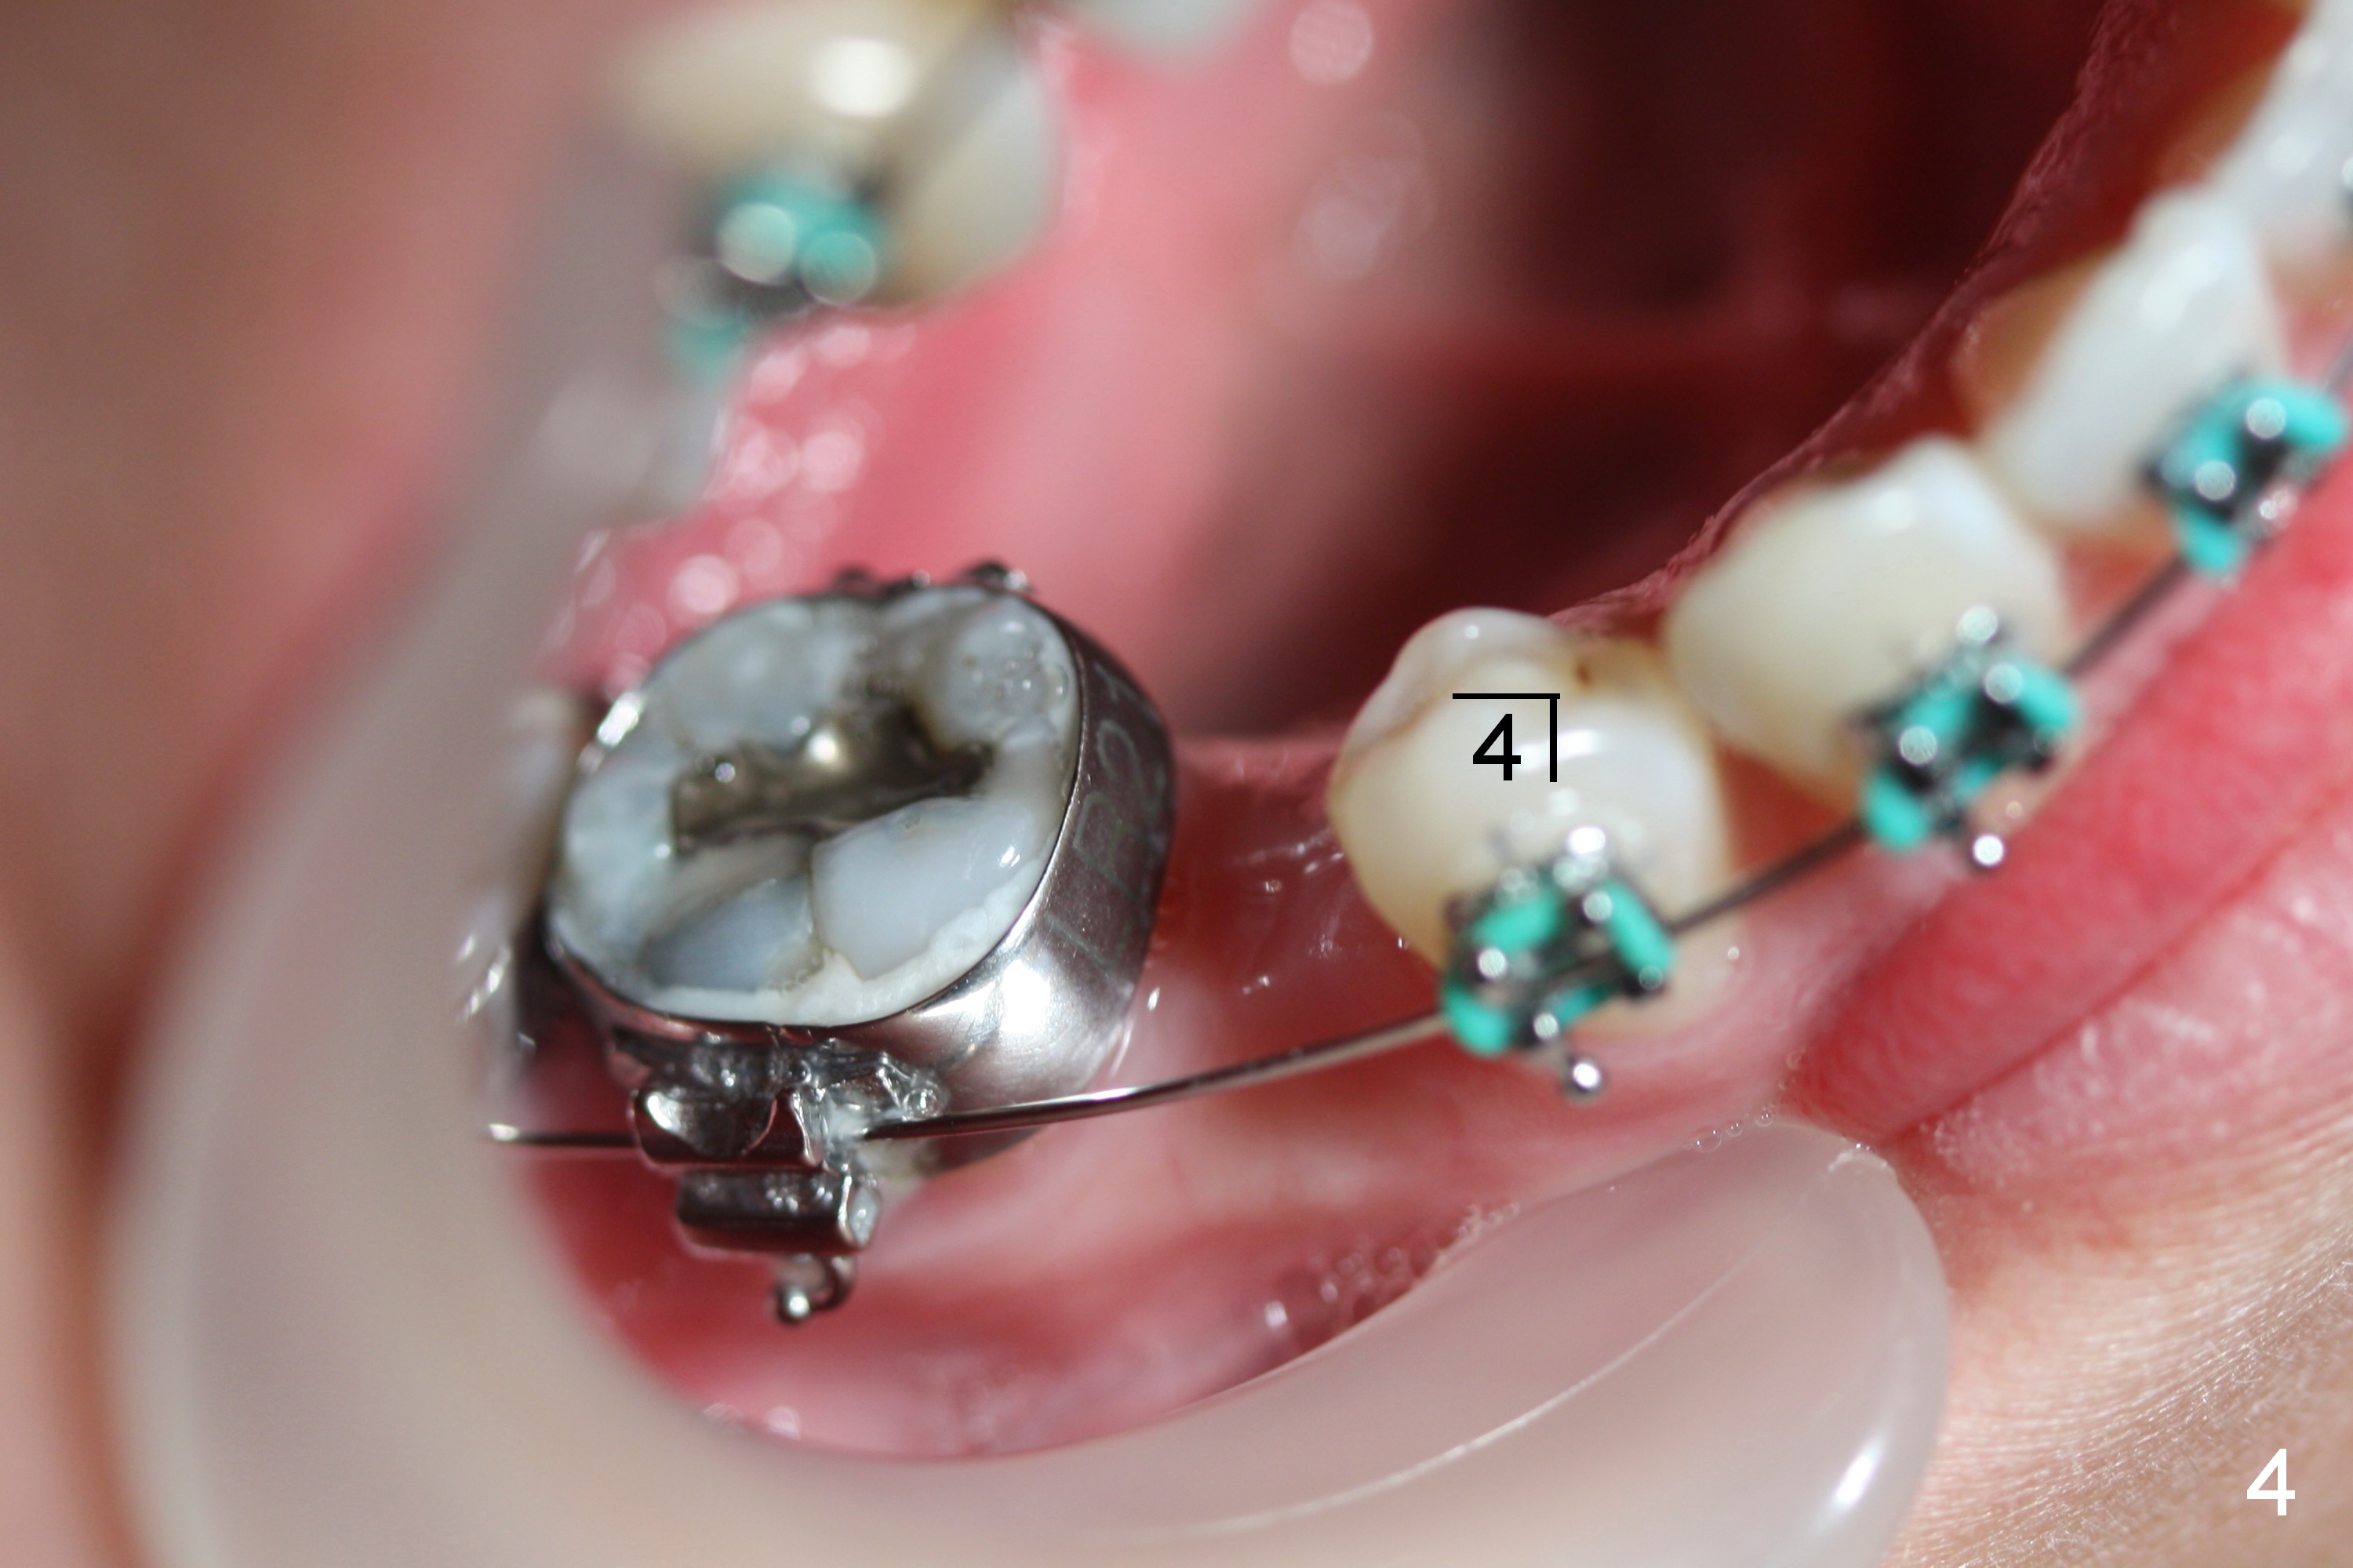

Next visit .016x.016" ss wires will be used. Two closed coil springs are placed between LR4 and 7 (Fig.4) and LL3 and 6 (Fig.5). The upper teeth will be retracted once the lower counterparts have achieved initial movement. Mini-implants are expected to be placed for upper retraction the following visit.

Four months post bracketing, two of 8 mm Ancor Mini-implants are placed at the sites of the upper 2nd molars and power chain of 3 placed between the 1st molars and the mini-implants (Fig.6,8). Niti Closing Springs (12 mm and 9 mm) are placed between LR4 and 7 and LL 3 and 6, respectively (Fig.7,9, 16x16 ss wires). The forces are 100 and 150 mg, respectively.